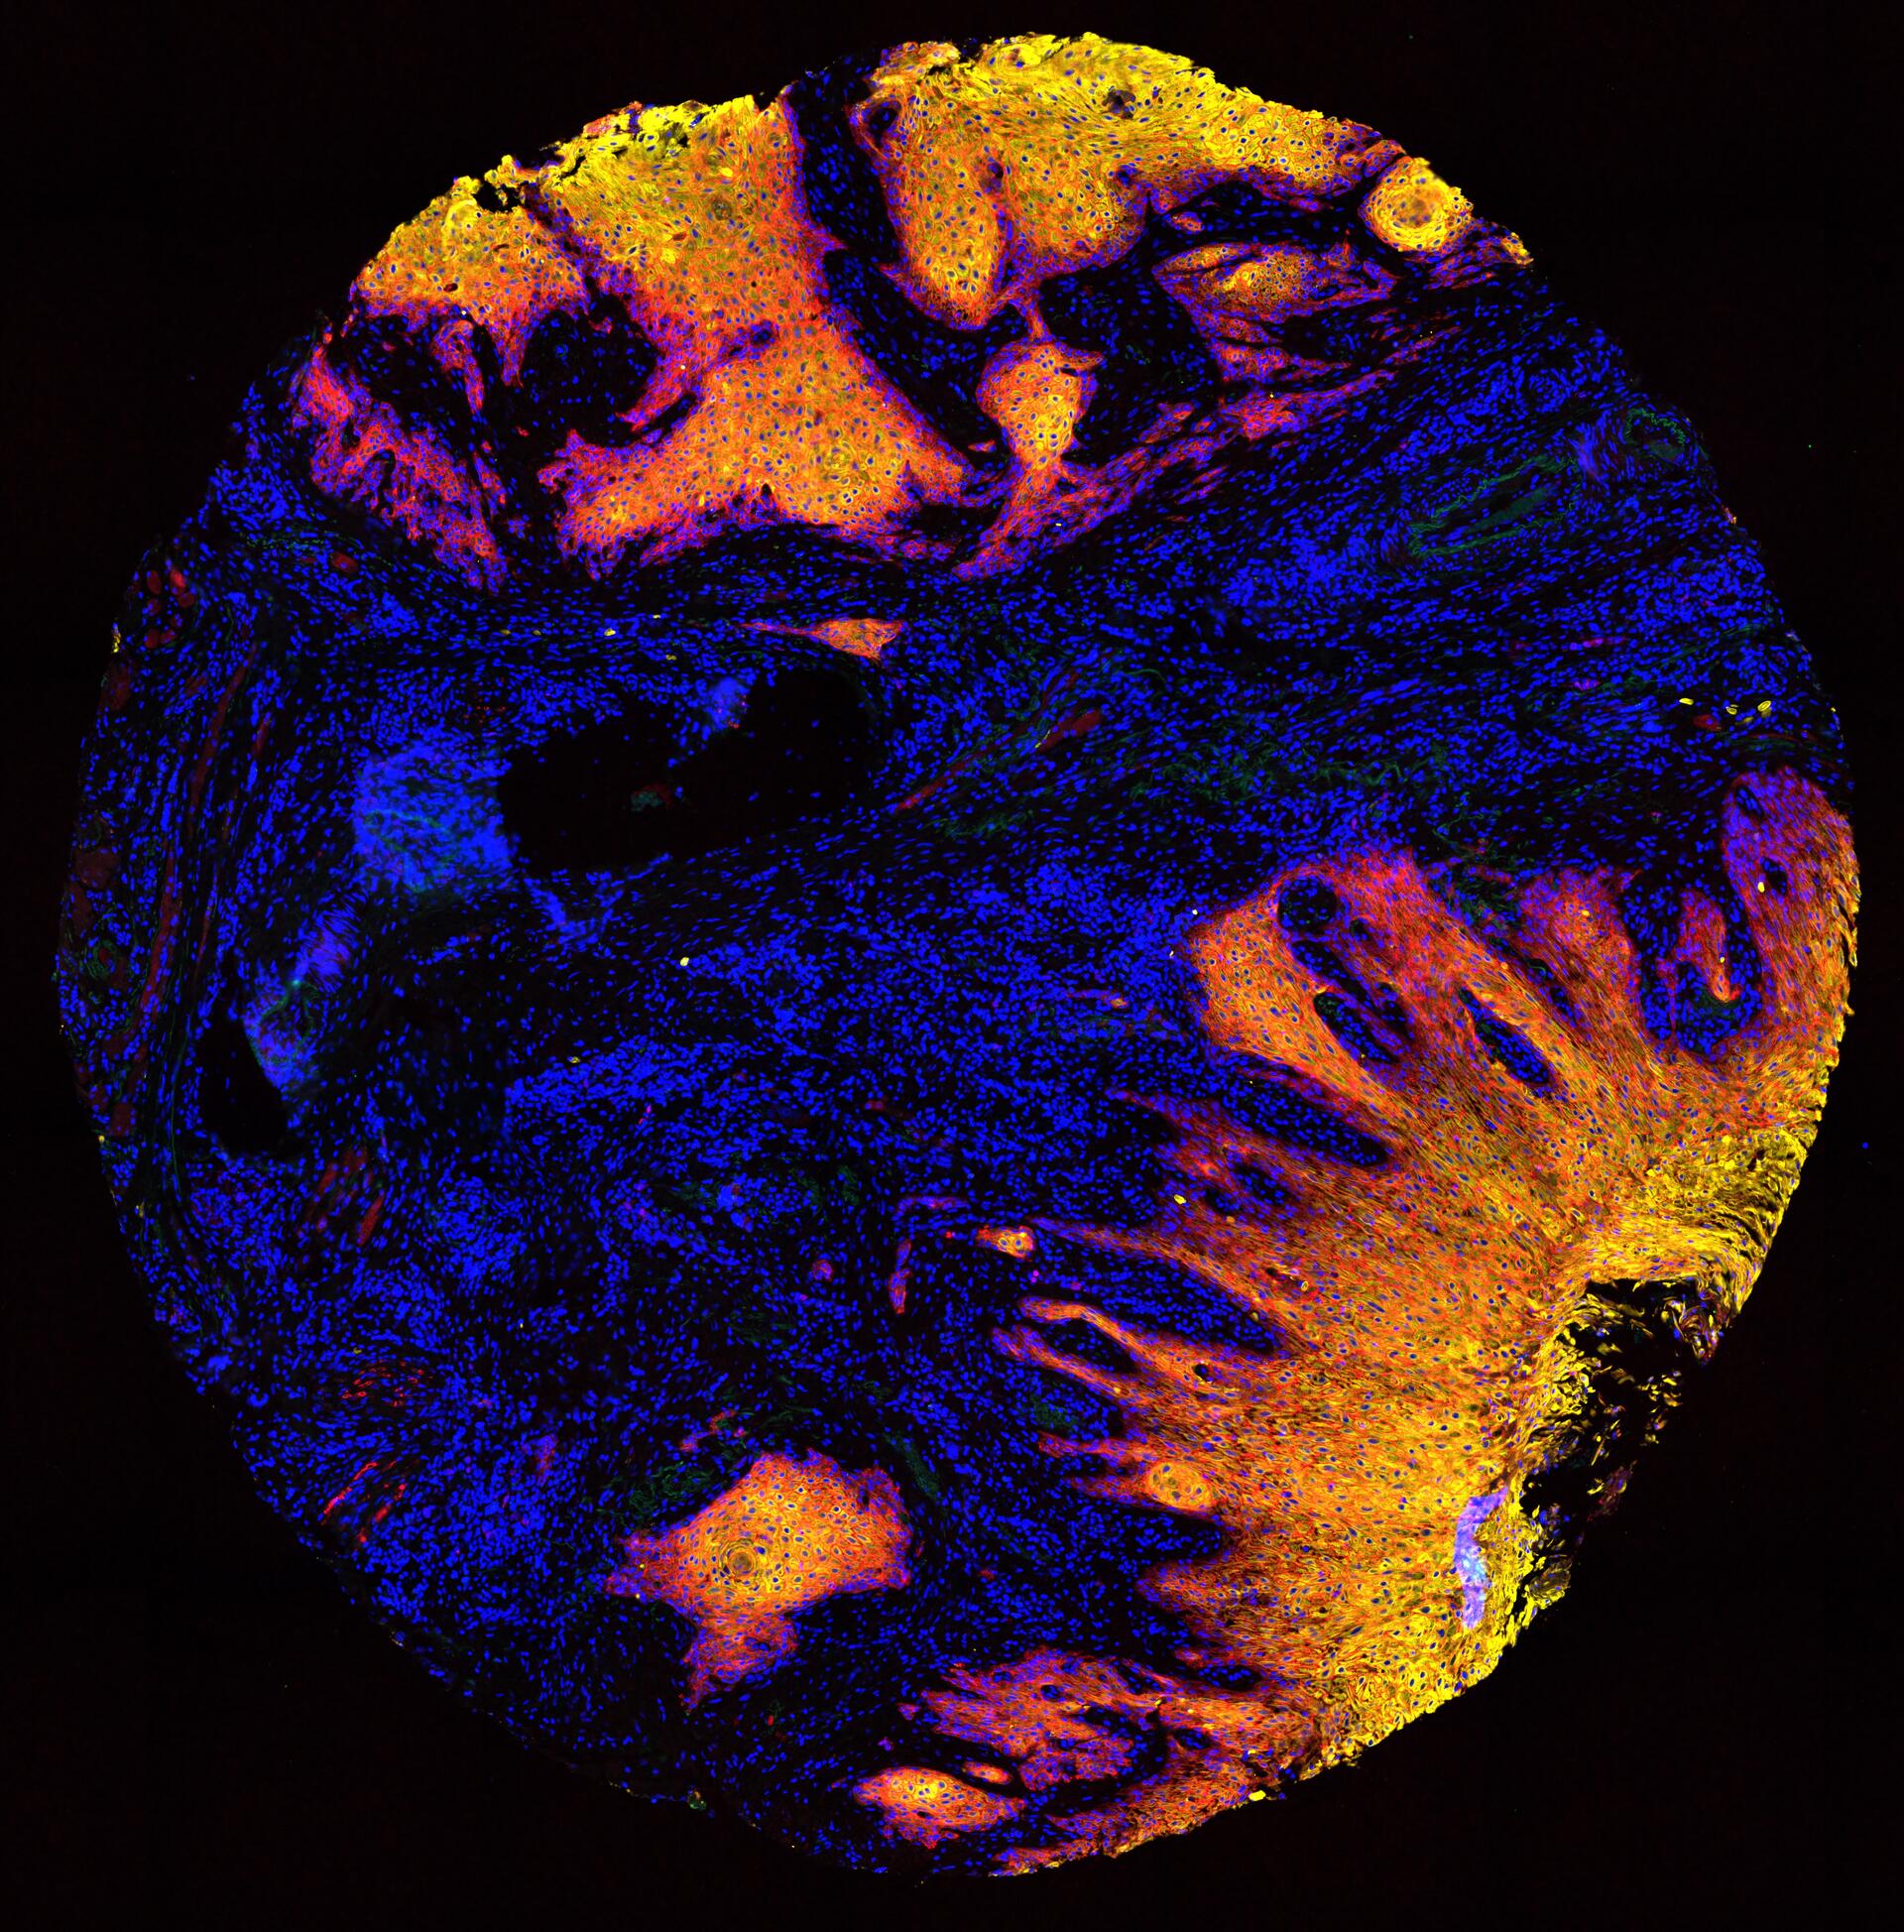

To understand: the basic molecular and cellular mechanisms in carcinogenesis, the progression of cancer as a biological process driven by natural selection, cellular mechanisms explaining early and late dissemination, present and emerging strategies for cancer therapy, cancer drug development